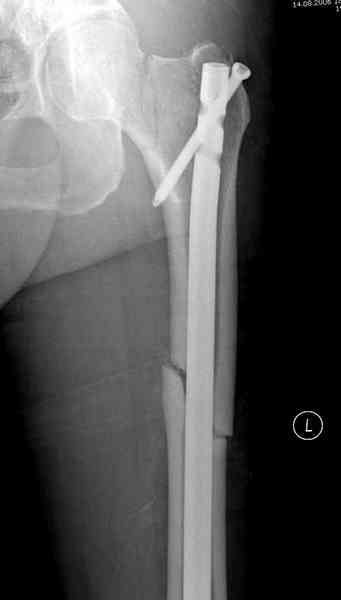

Здесь представлены снимки больного 65 лет, поступившего с диагнозом перелом

бедра после автоаварии.

В первый же день произведено антеградное штифтованием DePuy Trochanteric Nail.

На второй день (7) обнаружен пропущенный перелом,

сделаны Компьютерная Томограмма

и проведены шурурпы через и спереди штифта без удаления.

Послеоперационные снимки